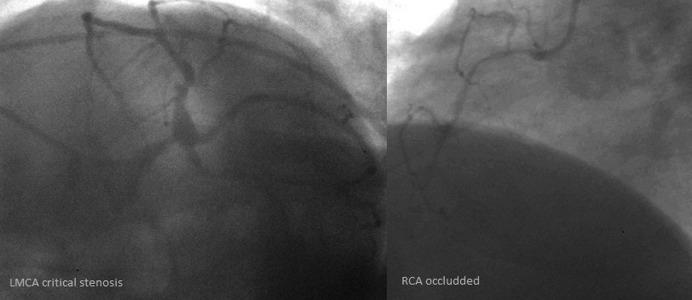

Coexistent carotid artery stenosis (CS) and multivessel coronary artery disease (CAD) is not infrequent. One in 5 patients with multivessel CAD has a severe CS, and CAD incidence reaches 80% in those referred for carotid revascularization. We reviewed treatment strategies for concomitant severe CS and CAD. We performed a literature search (MEDLINE) with terms including carotid artery stenting (CAS), coronary artery bypass grafting (CABG), carotid endarterectomy (CEA), stroke, and myocardial infarction (MI). The main therapeutic option for CS-CAD has been (simultaneous or staged) CEA-CABG. This, however, is associated with a high risk of MI (in those with CEA prior to CABG) or stroke (CABG prior to CEA), and the cumulative major adverse event rate (MAE - death, stroke or MI) reaches 10-12%. With increasing adoption of CAS, a sequential strategy of CAS followed by CABG has emerged. Registries (usually single-centre) indicate an MAE rate of ≈7% for CAS followed by CABG (frequently after >30 days, due to double antiplatelet therapy). Recently, 1-stage CAS-CABG has been introduced. This involves different antiplatelet regimens and, in some centers, preferred off-pump CABG, with a cumulative MAE of 1.4-4.5%. No randomized trial comparing different treatment strategies in CS-CAD has been conducted, and thus far reported series are prone to selection/reporting bias. In addition to the established surgical treatment (CEA-CABG, sequential/simultaneous), hybrid revascularization (CAS-CABG) is emerging as a viable therapeutic option. Larger, preferably multi-centre, studies are required before this can become widely applied.

同时存在颈动脉狭窄(CS)和多支冠状动脉疾病(CAD)并不罕见。5 分之一的多支 CAD 患者存在严重的 CS,而在那些需要进行颈动脉血运重建的患者中,CAD 的发生率达到 80%。我们回顾了同时存在严重 CS 和 CAD 的治疗策略。我们使用颈动脉支架置入术(CAS)、冠状动脉旁路移植术(CABG)、颈动脉内膜切除术(CEA)、中风和心肌梗死(MI)等术语进行了文献检索(MEDLINE)。CS-CAD 的主要治疗选择一直是(同期或分期)CEA-CABG。然而,这与 MI(在 CEA 之前进行 CABG 的患者中)或中风(在 CABG 之前进行 CEA 的患者中)的高风险相关,累积主要不良事件率(MAE-死亡、中风或 MI)达到 10-12%。随着 CAS 的广泛应用,出现了 CAS 后序贯 CABG 的策略。登记处(通常为单中心)表明,CAS 后序贯 CABG 的 MAE 率约为 7%(由于双联抗血小板治疗,通常在 30 天后进行)。最近,引入了 1 期 CAS-CABG。这涉及不同的抗血小板治疗方案,在一些中心,更倾向于非体外循环 CABG,累积 MAE 为 1.4-4.5%。目前尚未进行比较 CS-CAD 不同治疗策略的随机试验,到目前为止,报告的系列研究容易受到选择/报告偏倚的影响。除了既定的手术治疗(CEA-CABG、同期/序贯)之外,杂交血运重建(CAS-CABG)正在成为一种可行的治疗选择。在广泛应用之前,需要进行更大的、最好是多中心的研究。